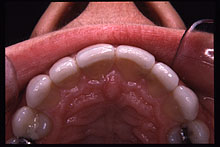

| Foto 4A.- Dientes 12 y 22 conoides. Vista frontal |

Foto 4B.- Carillas de porcelana en 11, 12, 21 y 22. Vista Frontal. |

En

este tipo de malformación dentaria, las carillas de porcelana han de

ser muy amplias para cerrar los espacios interproximales.

| Foto

4C.- Dientes 12 y 22 conoides. Vista oclusal. |

Foto 4D.- Carillas de porcelana en 11, 12, 21 y 22. Vista oclusal. |

De

esta forma, en muchos casos vienen a tener la forma casi de una corona de recubrimiento

total con una terminación cervical en filo de cuchillo.